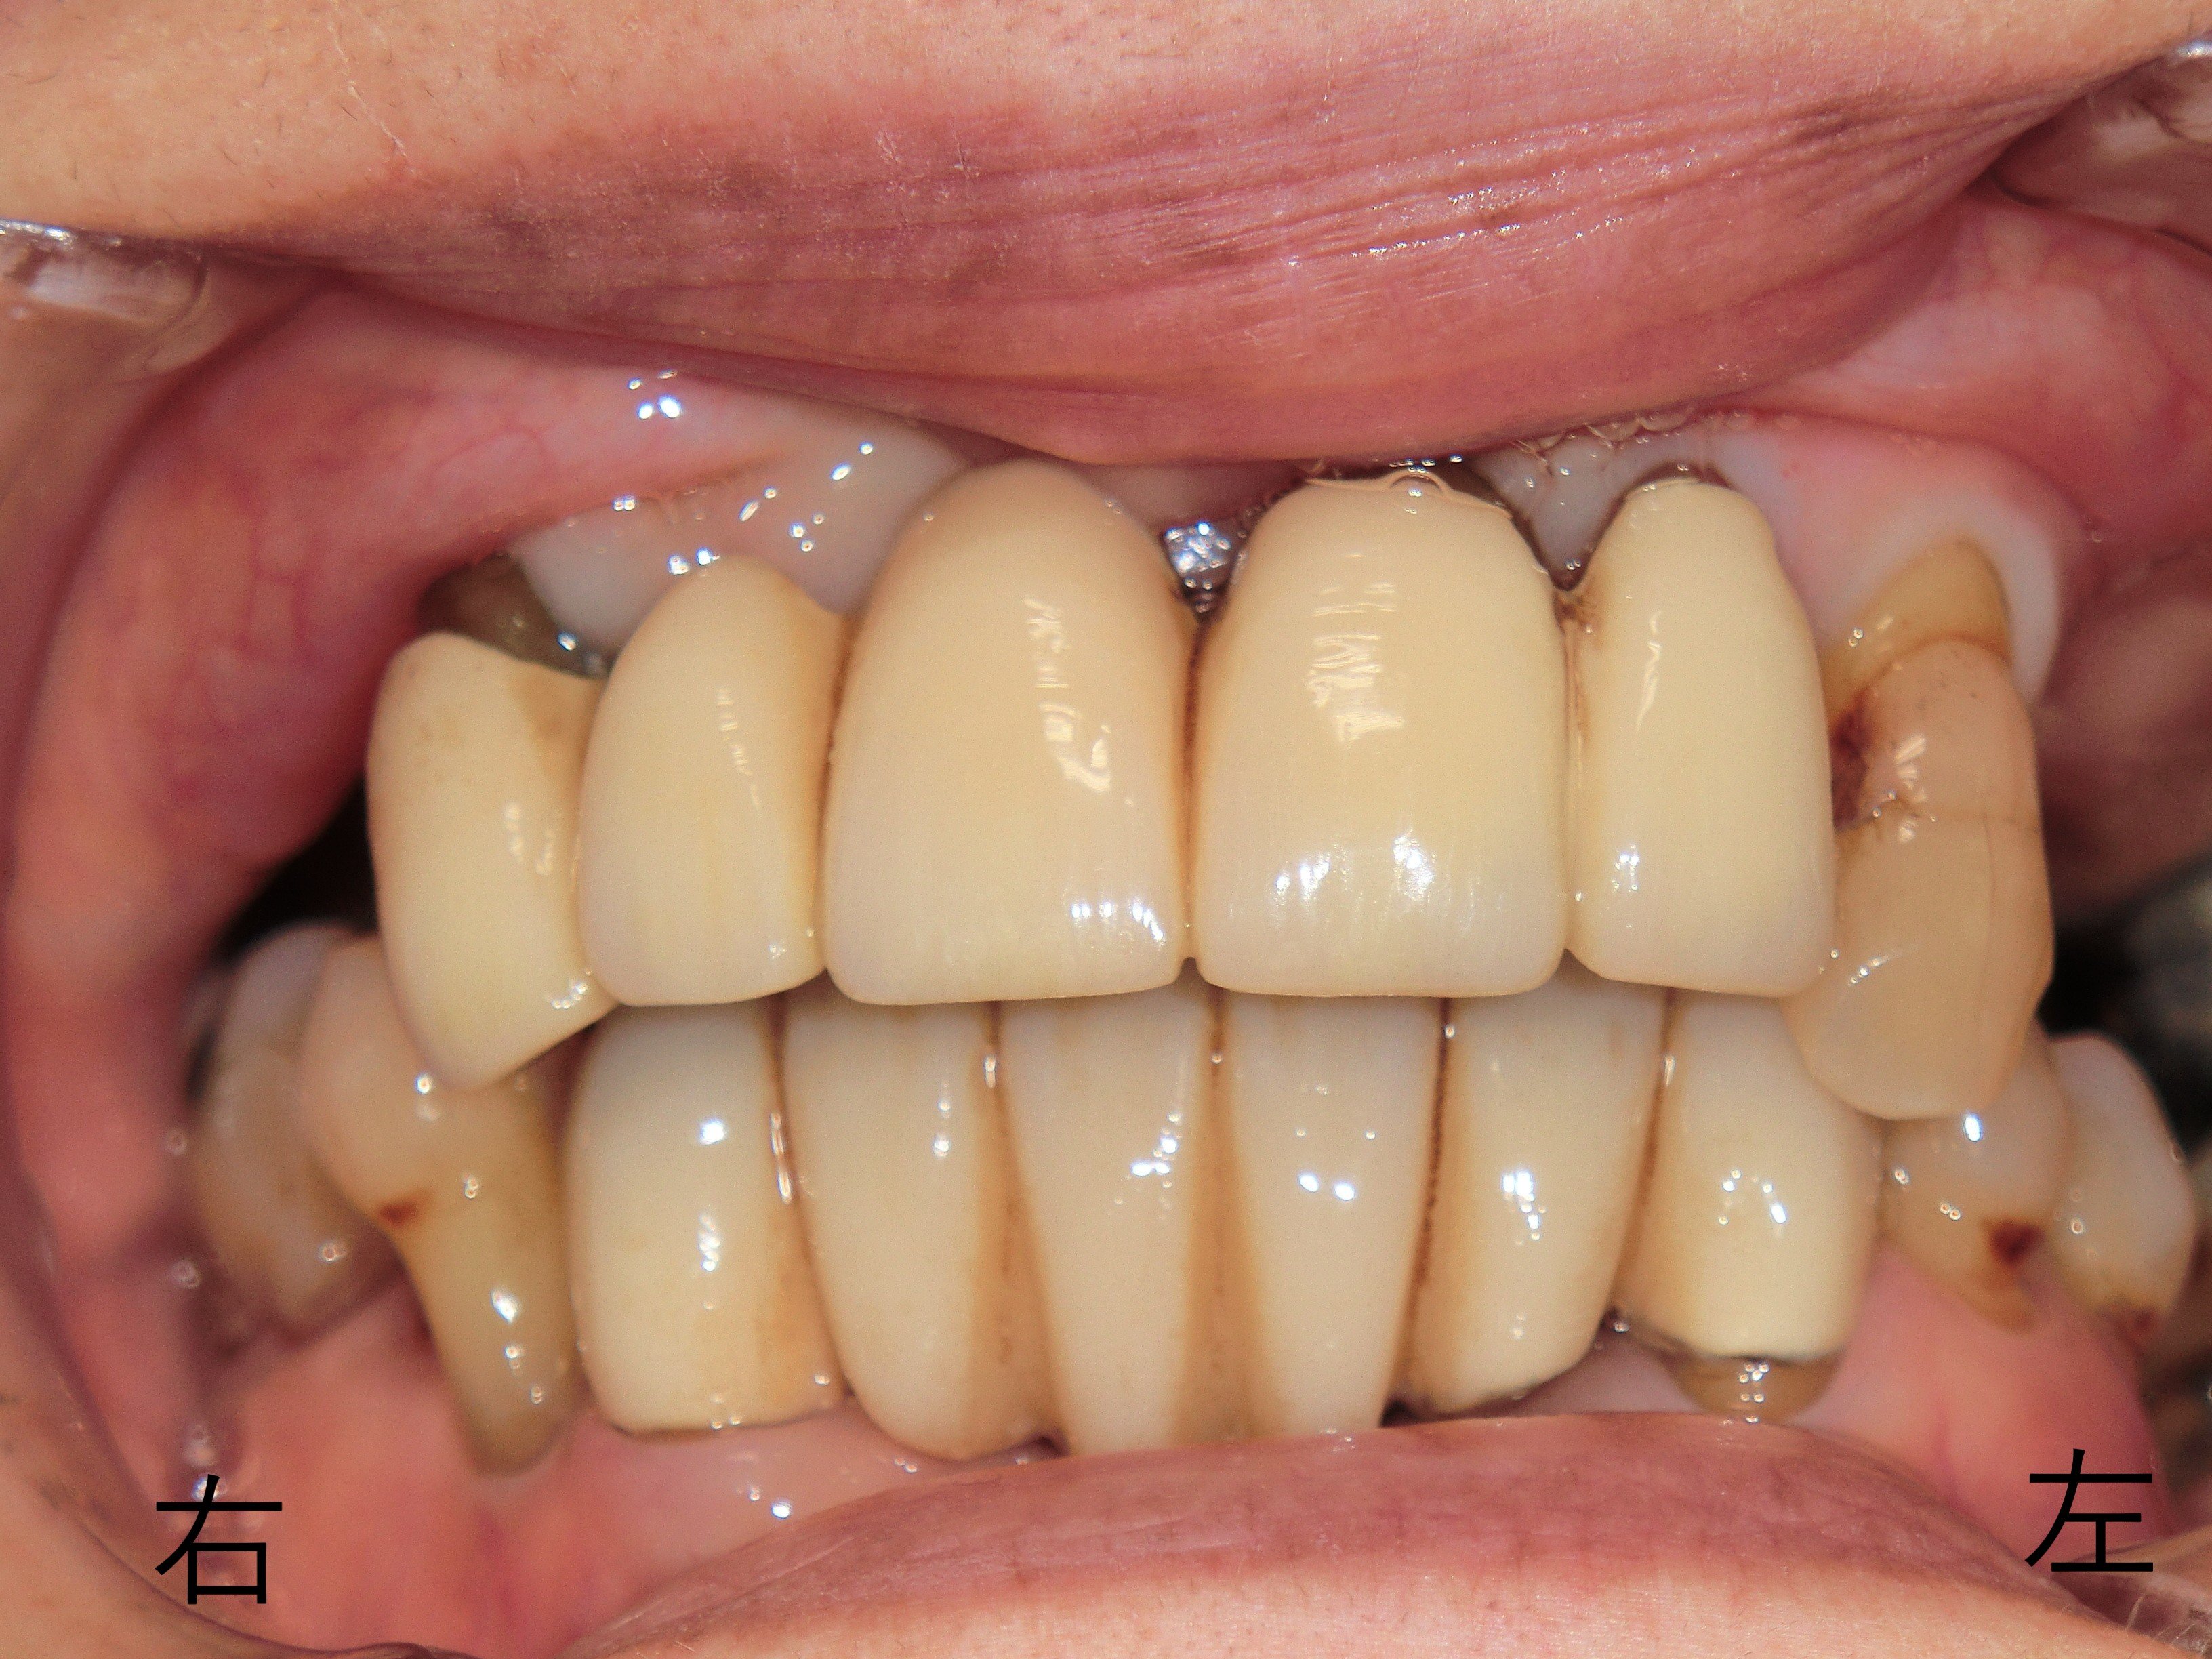

【初診時の状況】

長期間入れ歯を使用されておらず、主に前歯で噛む生活が続いていたため、前歯に過度な負担がかかり、上下ともに動揺(グラつき)が顕著となっていました。加えて、歯周病の進行により全体的な治療が必要と判断されました。

【レントゲンおよび口腔内診査】

歯槽骨の吸収が著しく、全体的な歯周病の進行が確認され、初診時点では詳細な治療計画を立てるのが困難な状況でした。さらに、長期間の義歯不使用により右下奥歯が挺出していた(歯が伸びていた)ことも確認されました。